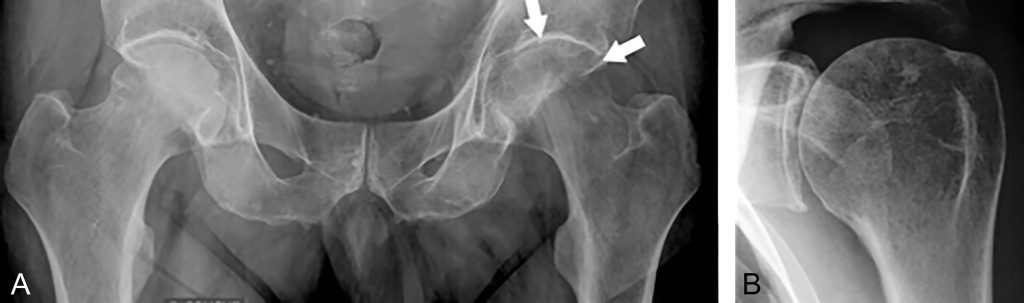

Fig. 85.1 Radiographies.

(A) SDRC 1 de la hanche gauche. Radiographie du bassin de face montrant une déminéralisation de la tête fémorale gauche (flèches) sans pincement de l’interligne. (B) SDRC 1 de l’épaule gauche. Radiographies de face de l’épaule montrant une déminéralisation pommelée de topographie sous-chondrale.

Source : CERF, CNEBMN, 2022.